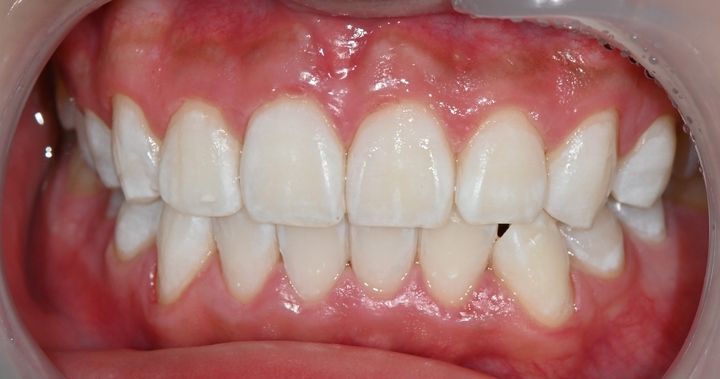

ハル歯科医院は、最先端のインプラント歯科治療に特化したクリニックです。代表のジョー・ハング院長は日本の神奈川歯科大学を卒業し、両国での歯科医師免許を保持。さらに、韓国で専門医資格を取得し、口腔外科など高度な手術経験も豊富です。すべての治療を院長自らが行う専任診療制を採用しており、流暢な日本語で対応可能。「デジタルインプラント」や「無削除ラミネート」などの最新のデジタル歯科治療を、日本の約半額で受けられます。仁川・金浦空港から乗り換えなしで行ける孔徳(コンドッ)駅すぐとアクセスも良好で、旅行者にも便利な立地となっています。

近所に住んでいる日本人でホワイトニングで訪れました。先生は日本語が流暢で歯科衛生士さんも少し日本語で対応していただけた為、安心感があります。一回のホワイトニングで歯が綺麗になったのでとても嬉しかったです。

今回ホワイトニングを1回受けました!

歯の色もすぐ白くなったし、凍みることもなかったです!